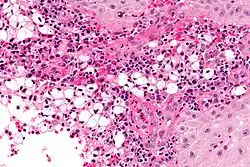

Micrograph showing abundant subepithelial histiocytes in a case of rhinoscleroma. H&E stain.

A positive culture in MacConkey agar is diagnostic, but cultures are only positive in 50–60% of cases. Diagnostic characteristics are most commonly found in the granulomatous stage and are described as being plasma cells with birefringent inclusions, Russell bodies, pseudoepitheliomatous hyperplasia, and groups of large vacuolated histiocytes containing Klebsiella rhinoscleromatis (Mikulicz cells).[2]